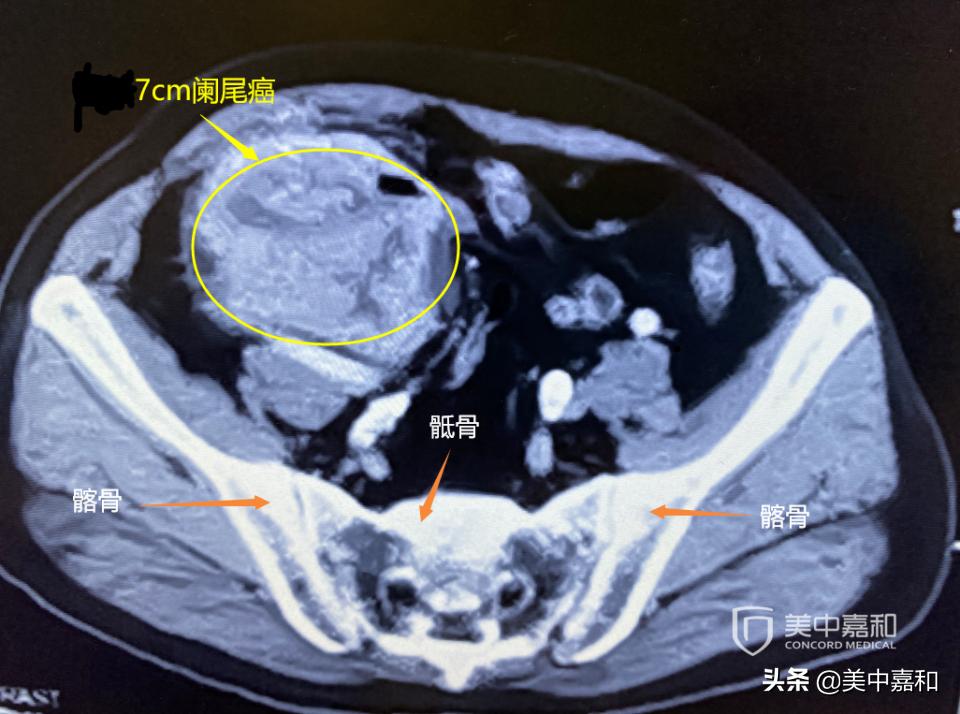

画圈处为最大径7cm阑尾癌

此次参加多学科会诊的李先生,四月初断断续续腹部隐痛,到医院检查发现了七八厘米的肿块。月底动手术,确诊为阑尾癌,与回肠、结肠粘连,肿瘤最大径为7cm,侵透肌层累及浆膜。

2020.04.23行右半结肠切除术。术中见回盲部直径7cm肿块,源发于阑尾,侵出浆膜外,未扪及肿大淋巴结,并行手术切除肿瘤。术后病理:(右半结肠切除标本)阑尾、回肠弥漫浸润型中分化腺癌,肿瘤主体位于阑尾体尾部,与回肠、结肠粘连,肿瘤最大径7cm,侵透肌层累及浆膜。未累及回盲瓣,上、下切缘阴性。肿物旁淋巴结0/13;IHC: P53突变,HER2-,EGFR+,TOP-,C-myc-,BRAF+, MLH1+, MSH2+, MSH6+, PMS2+。